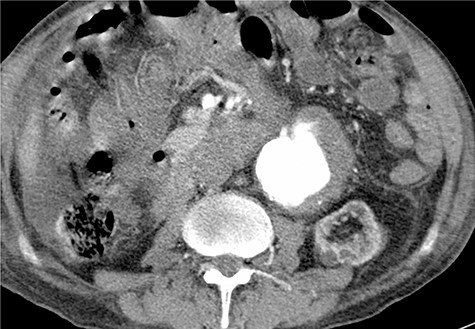

Given the rapid decompensation in the patient, a simultaneous liver-kidney transplant was proposed, but because the accepted diameter of aneurysm for surgical management is 5.5 cm and higher [1], it was decided to closely follow-up with the patient post-transplantation. The liver was transplanted using the piggy-back technique, inferior vena cava was anastomosed side-to-side, and portal veins and hepatic arteries were anastomosed end-to-end. The donor kidney was placed in the right iliac fossa with anastomosis of the right internal iliac artery and vein in an end-to-end fashion. The patient then had an uncomplicated post-operation course and was discharged with an immunosuppressive regimen. One month later, the patient came to the emergency room with severe abdominal pain. To rule out possible aneurysm rupture, an emergent CT scan with contrast was performed; however, the findings were compatible with an infrarenal aortic aneurysm with eccentric mural thrombosis. In addition, the aneurysm had grown in size and had a diameter of 5.2*6.5 (Fig. 2).